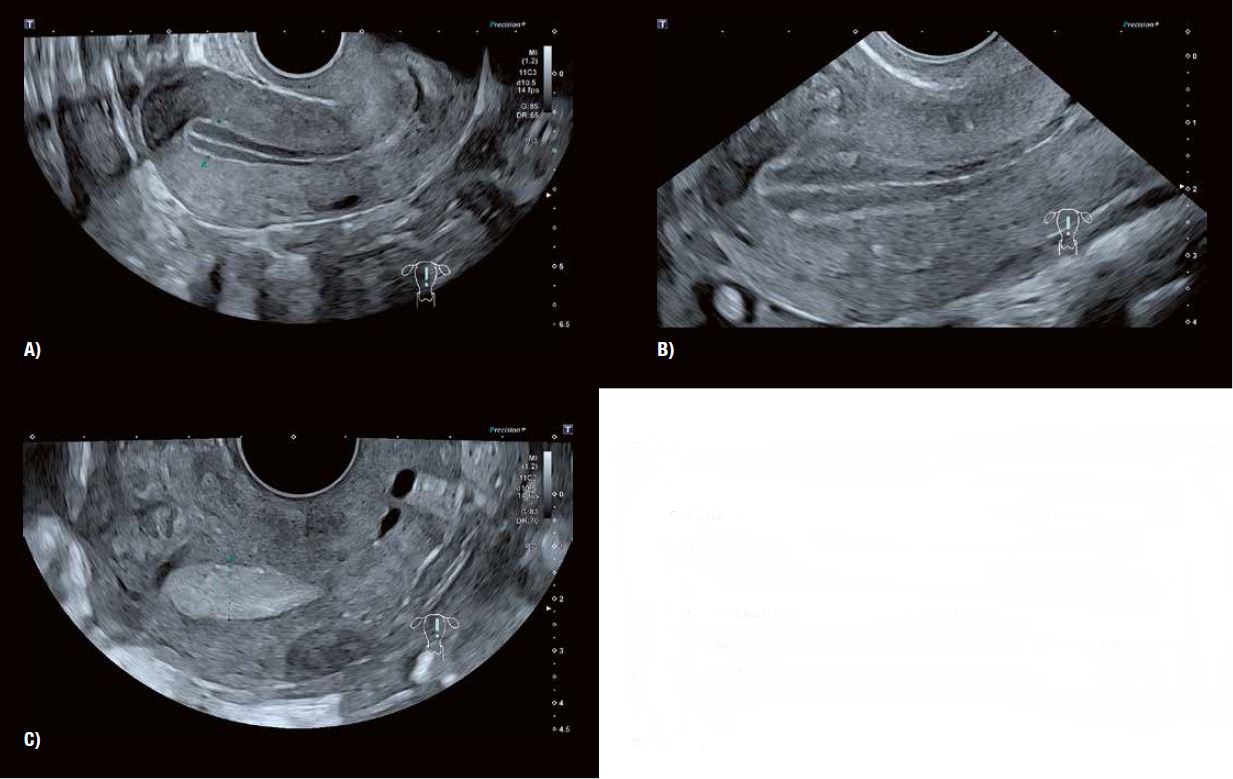

Рис. 6 А: Сприятливий вигляд ендометрію через 24–30 годин після ін'єкції препарату, що стимулює овуляцію.

Рис. 6 Б: SMI підтверджує наявність активного, зрілого фолікула перед овуляцією, що призводить до змін ендометрія в період овуляції, описаних на рис. 6 А.

Рис. 6 В: Зображення Fly Thru демонструє ймовірну масу кумулюса, що вільно плаває у фолікулярній рідині перед овуляцією.

Рис. 7 A, B і C: Серія зображень втрансвагінальним датчиком показує характерні зміни в зовнішньому вигляді ендометрію під час переходу від середньої фази проліферації (A) до фази овуляції (B) і ранньої фази жовтого тіла (C). Зміна характеристик сірої шкали відображає стадії проліферації залоз у стромі ендометрію. У міру збільшення залоз ендометрію тканина стає більш ехогенною і «яскравою» на ультразвуковому зображенні порівняно з навколишнім міометрієм. Сучасна візуалізація трансвагінальним датчиком у сірій шкалі виключає термін «тришаровий» для опису циклічного розвитку ендометрі.